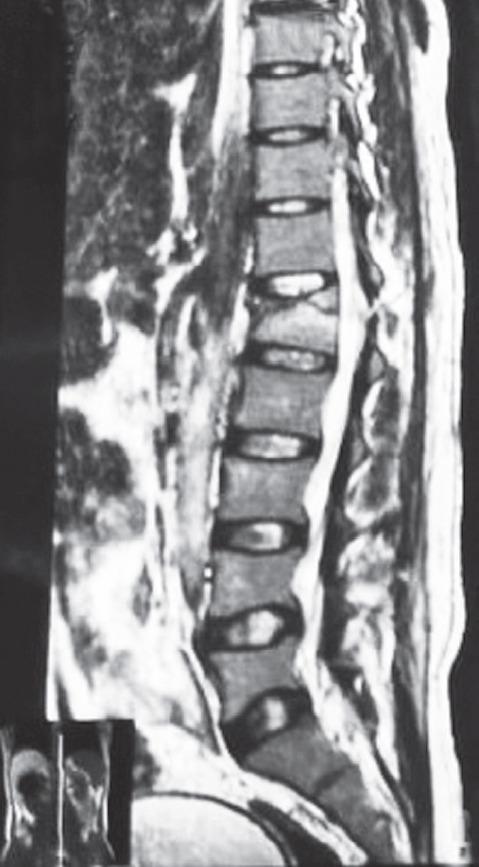

Patients who sustained injuries from T1 to L3 and required posterior surgery were prospectively studied. The treating surgeon and musculoskeletal radiologist participating in the study reviewed preoperative MRI images to characterize the level(s) of injury and the integrity of the six components of the PLC. These were classified as intact, incompletely disrupted, or disrupted. During the surgical procedure, the surgeon also classified each component of the PLC, and the radiologist's and surgeon's findings were compared.

对T1至L3受伤且需要进行后路手术的患者进行前瞻性研究。参与研究的主治外科医生和肌肉骨骼放射科医生回顾术前MRI图像,以确定损伤水平和PLC六个组成部分的完整性。这些被分类为完整、不完全断裂或断裂。在手术过程中,外科医生也对PLC的每个组成部分进行分类,并比较放射科医生和外科医生的检查结果。